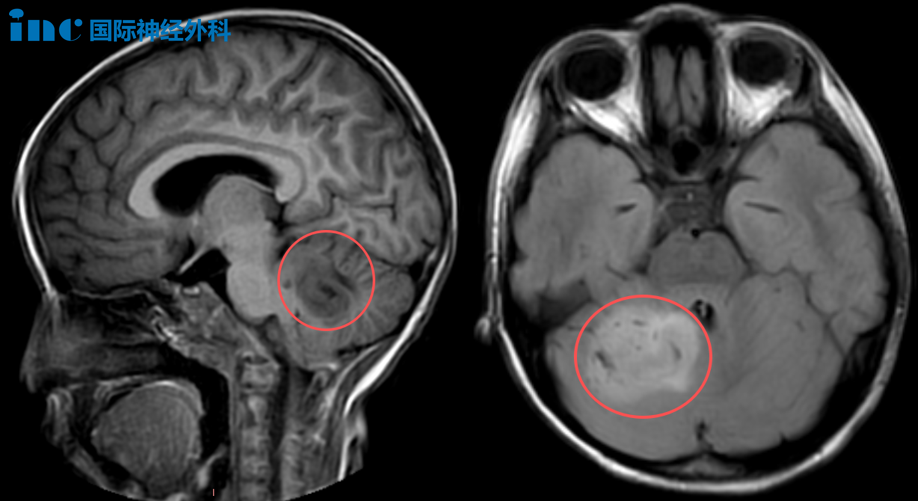

直至今年9月,放学回家的乐乐向父母说起自己白天总是头晕,还提不起力气。隔天晚上,由于乐乐多次呕吐,父母连夜将女儿送至医院就诊,可没想到就此查出了乐乐小脑里的巨大“怪兽”。

第二天,乐乐再次出现呕吐,并仍有头晕恶心的症状,于是医生建议入院治疗,而进一步的检查又一次证实了这个噩耗——乐乐的右侧小脑存在异常信号,考虑为低级别胶质瘤。另外,由于乐乐的抽血化验结果提示为胃肠型感冒,因此乐乐同步开始服药,直至头晕好转。

巴教授:“考虑到病灶体积,手术是必须要做的。即便是低级别肿瘤,也可能随时恶变,我们绝不能给肿瘤恶化的机会。脑干与小脑之间存在连接,尽管该病变部分涉及连接区域,但并未累及脑干本身。对他们而言,切除难度较大,但对我来说并非难事,我能做到。(手术)会在尽可能切除肿瘤的同时,保持患者的神经功能和生活质量。”

10月20日,属于乐乐的“冒险”开始了。手术由巴教授主刀,苏州大学附属儿童医院神外团队默契配合,并应用术中导航及术中超声,仔细确认肿瘤边界,最终在术中电生理监测的保驾护航下,手术顺利,肿瘤达到满意切除!病理显示肿瘤为低级别胶质瘤,这无疑让等候在手术室外的家人松了一口气。